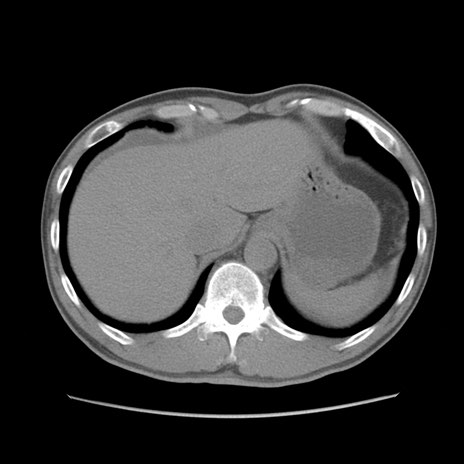

症例56 CT(横断像)

症例